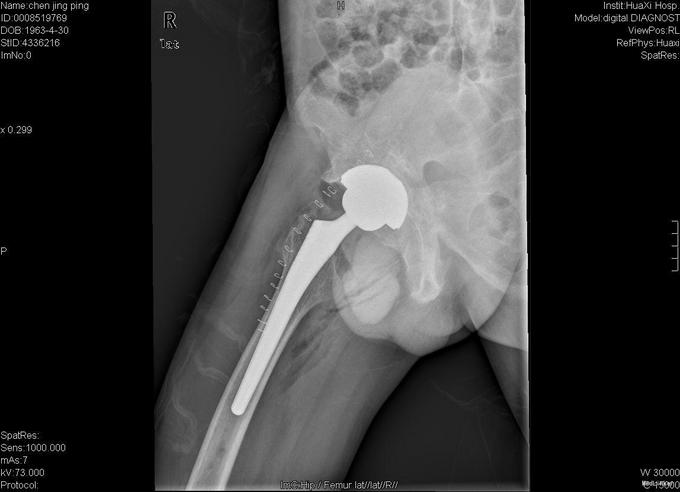

查体:跛行步态,强迫体位,脊柱强直后凸畸形,活动受限。右髋强直畸形,压痛、叩痛,无瘢痕、窦道,无皮损、皮癣,活动受限。双下肢感觉无明显异常。 辅助检查:x线片:脊柱呈"竹节样"改变,腰椎小关节间隙模糊,双侧骶髂关节及右髋关节间隙消失,骨性融合。

诊断:强直性脊柱炎 右髋关节强直 治疗:完善相关检查后在全麻下行右侧全髋关节置换术+髋臼成形术,手术顺利,术后予以抗炎+抗凝+阵痛等治疗。

术后患者恢复良好,右髋屈曲100°,伸直0°,外展40° 1、强直性脊柱炎起病特点有哪些 2、实验室检查及影像学表现有何特点? 3、治疗原则及主要治疗方法有哪些?